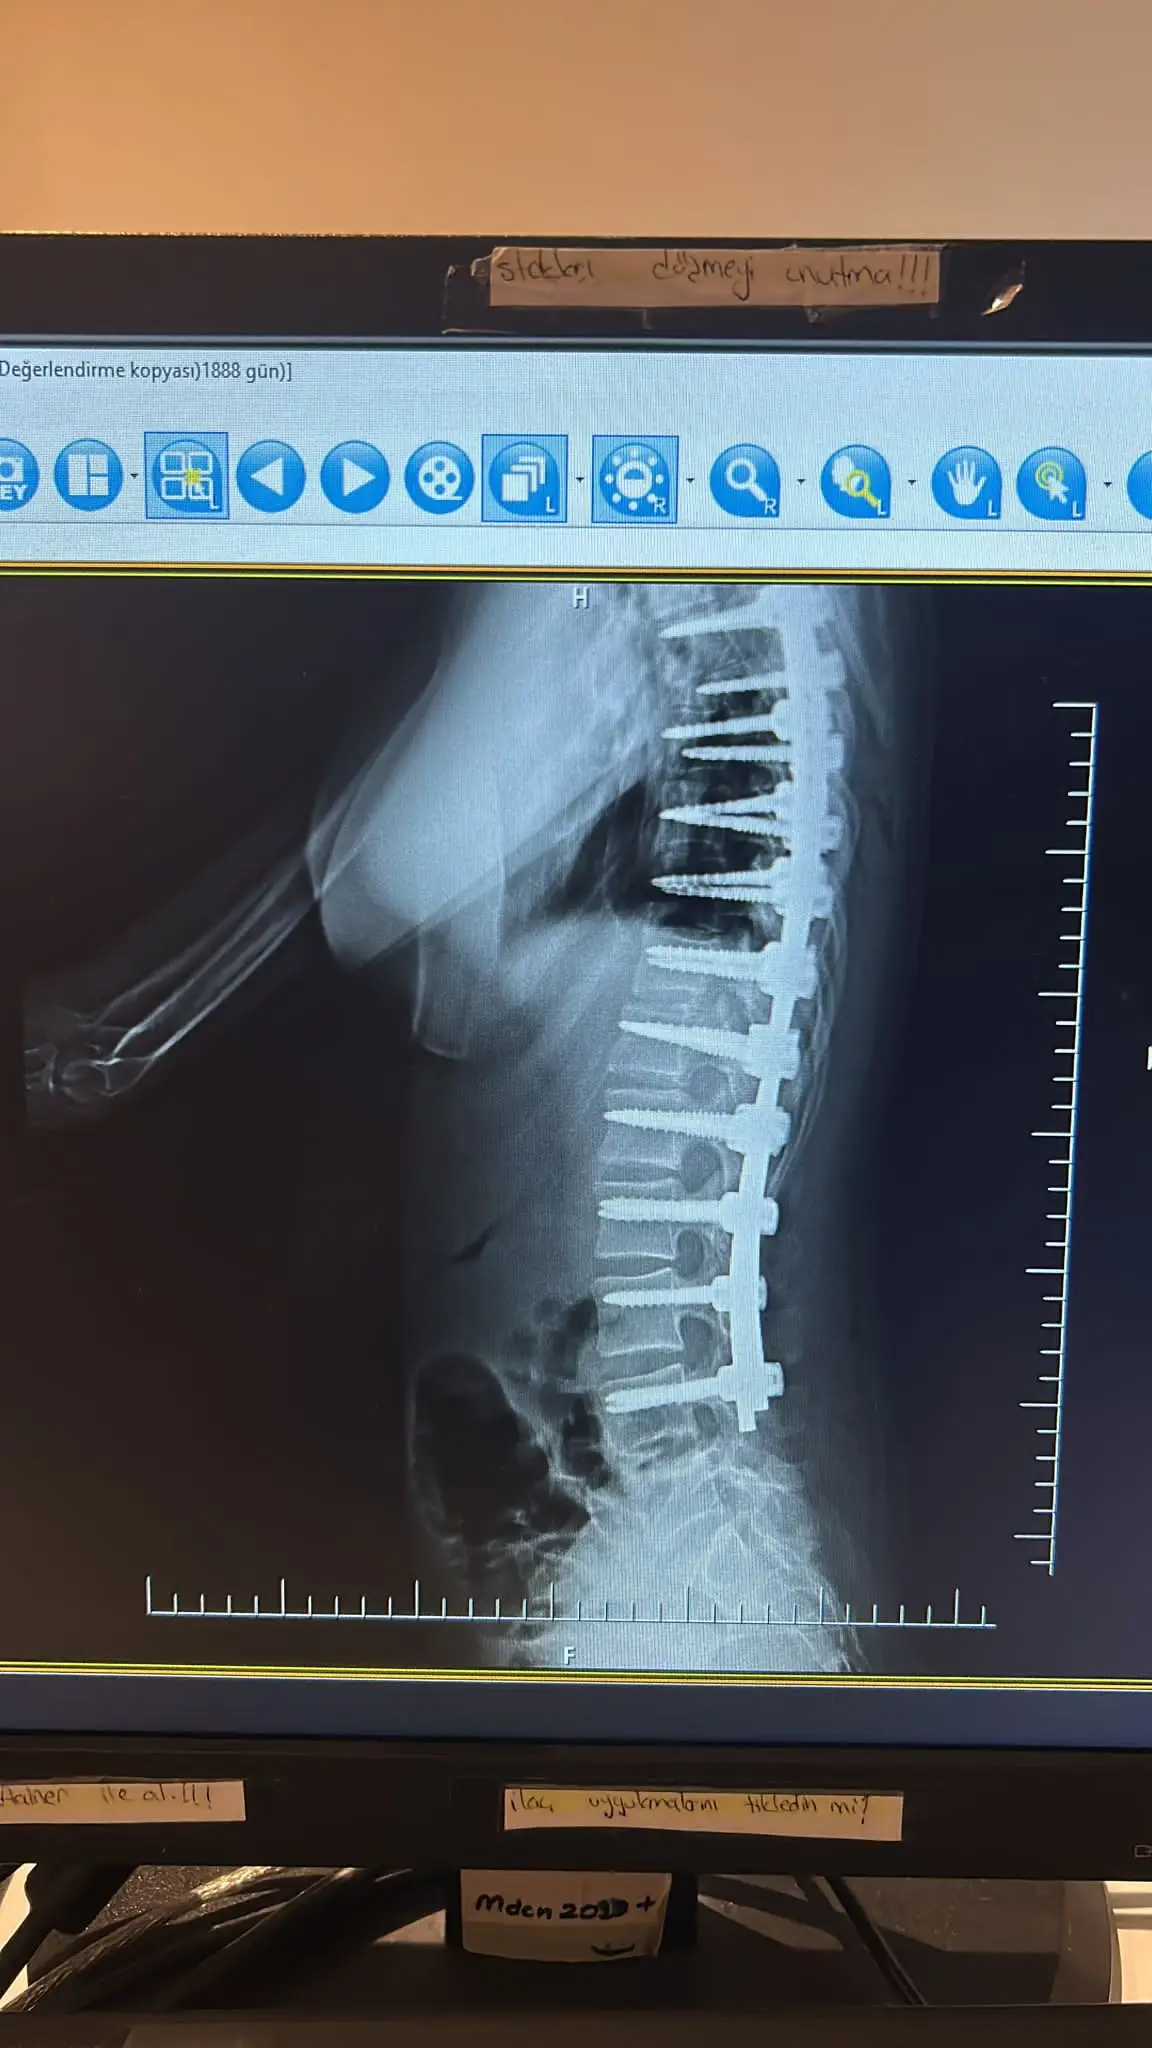

Hello, people with big hearts! Our lovely Aissy went through a second very difficult and complicated spinal surgery. Due to the abnormalities she has , more implants were placed than intended. She is in a serious condition and the scary panic attacks have started. He can't get out of bed and refuses to eat. Despite everything we with the help of the doctors , are fighting her condition to improve. For this purpose, however, the funds left in the account , are very insufficient. I ask you from my heart and soul, Help us , Icy to chase and fulfill her dreams! Share our campaign to reach as many people as possible to answer our cry for help! This beautiful child, has to live! Thank you! Take a bow!